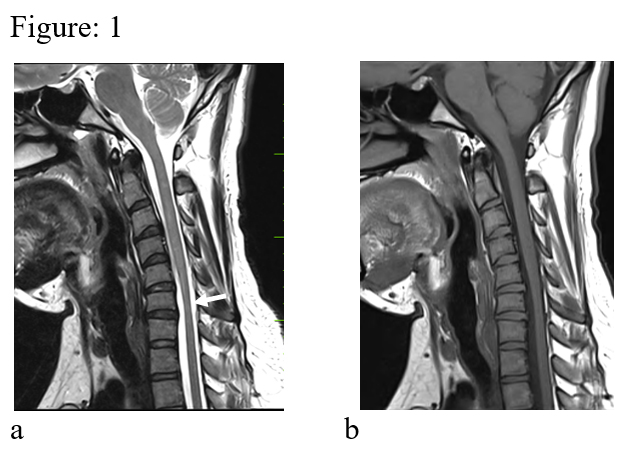

Figure: 1 (a & b). Sagittal T2 & T1 images in neutral position reveal localized cord atrophy (white arrow). No demonstrable dural displacement is seen.